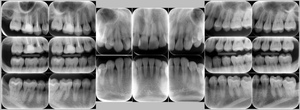

レントゲン写真

レントゲン写真

レントゲン写真を撮って、骨の状態を調べます。前回、または次回と比較し、進行状態や進行速度を判断します。